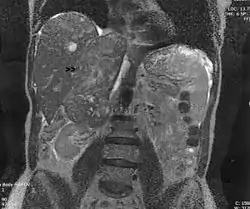

![]() ساركومة عضلية ملساء في الوريد الكظري. منظر إكليلي للتصوير بالرنين المغناطيسي على البطن. ويمتد الورم (السهم) من القطب العلوي للكلى اليمنى إلى الأذين الأيمن. ساركومة عضلية ملساء في الوريد الكظري. منظر إكليلي للتصوير بالرنين المغناطيسي على البطن. ويمتد الورم (السهم) من القطب العلوي للكلى اليمنى إلى الأذين الأيمن. | |